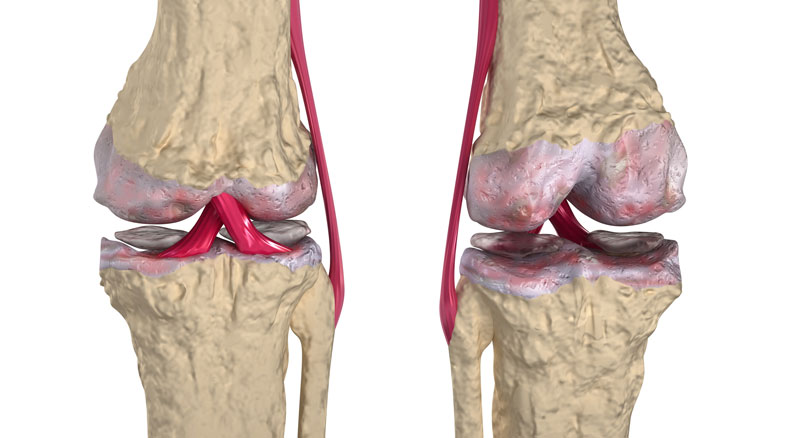

Професор Пак: У Китаї ми довели, що суглоби можуть повністю регенерувати, і їх можна і потрібно лікувати. Основна проблема хвороби - це зношування. Суглоби постійно піддаються високим навантаженням, тому хрящова тканина втрачає еластичність стоншується і зношується. Звідси біль, пухлини (грижа міжхребцевого диска) та деформація кісток (остеоартроз). До 60 років багато людей вже втратили 45-50% свого хряща. Як можна відновити те, чого вже немає? Чи можна буквально "побудувати" суглоб? Так, можна!

Кореспондент: Як виглядає процес відновлення?

Професор Пак: Доведено, що клітини, які відповідають за здоров'я та ріст хрящової тканини розташовані всередині нього.. Складники OsteoFixу не тільки знімають набряк, біль і запалення, але й безпосередньо впливають на ці клітини і активізують їх розподіл. Іншими словами, цей продукт активує сплячий механізм і змушує його працювати швидше. Засіб OsteoFix посилює кровообіг в навколишніх тканинах, що призводить до до розмноження рідини в суглобовій капсулі. Це збільшує рухливість самого суглоба і дозволяє йому прискорити зростання хрящової тканини. Що стосується злоякісних пухлин (гриж), то вони поступово пом'якшуються під впливом препарату і виводяться з організму спочатку кров’ю, а потім природним шляхом, просочуючись у кишечник.